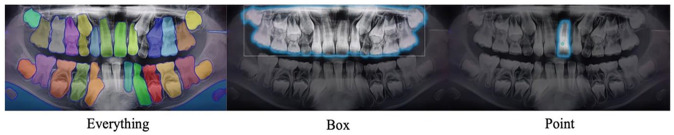

Objective: The aim is to detect impacted teeth in panoramic radiology by refining the pretrained MedSAM model.

Study design: Impacted teeth are dental issues that can cause complications and are diagnosed via radiographs. We modified SAM model for individual tooth segmentation using 1016 X-ray images. The dataset was split into training, validation, and testing sets, with a ratio of 16:3:1. We enhanced the SAM model to automatically detect impacted teeth by focusing on the tooth's center for more accurate results.